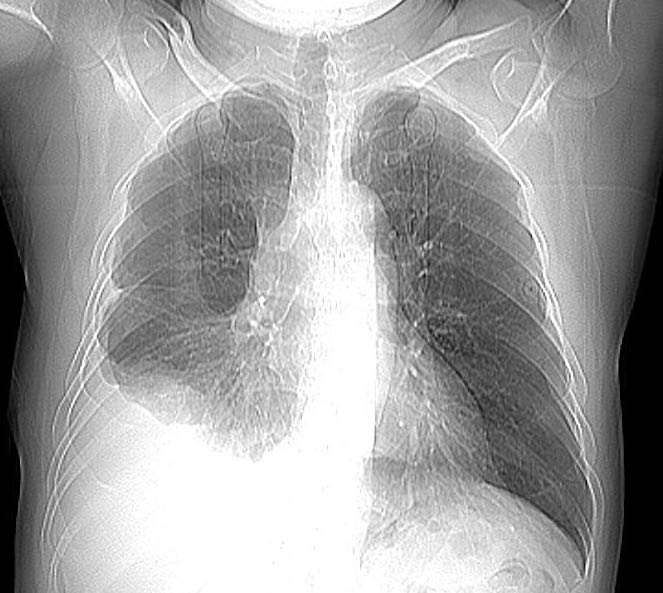

男,56岁,右侧腋窝下巨大软组织包块转移。欢迎讨论。

该病例为已经确诊的右侧恶性胸膜间皮瘤病例,有青石棉接触史,早期就是胸水,右侧胸壁“花边状改变”,心隔角区软组织阴影形成。近期右侧腋窝下巨大软组织包块,病检为转移瘤。图片没有完全考来,主要是给大家看一下胸膜间皮瘤的病例。,右侧

右侧腋窝下巨大软组织包块已经被切除后的ct片,该病例有多家医院较多的ct检查片。